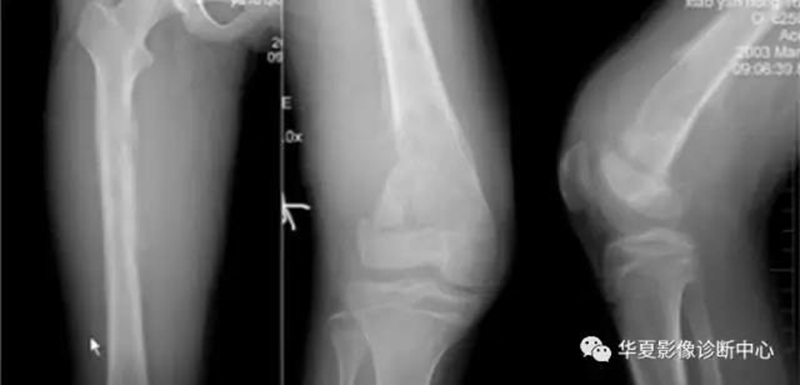

股骨远端正常骨骺,侵犯骺板软骨:出现软组织且宽窄不一